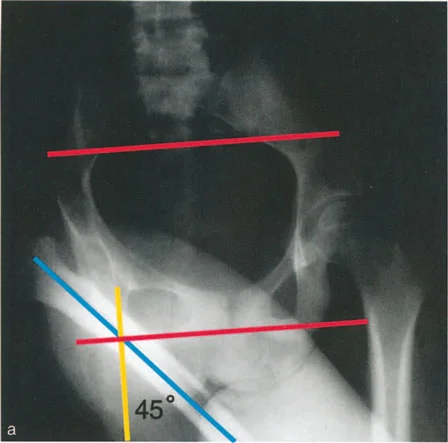

رسم توضيحي لتقييم ما قبل الجراحة لأقصى تقريب لعظم الفخذ (اختبار التقريب المتقاطع للساقين). في هذا المريض، تبلغ زاوية التقريب القصوى 45 درجة بالضبط.

1. أقصى تقريب سلبي: يتم قياسه على صورة أشعة سينية للمريض مستلقيًا مع تقاطع الساق المصابة فوق الفخذ المقابل إلى أقصى حد.

2. زاوية هبوط الحوض عند الوقوف على ساق واحدة: يتم قياسها على صورة